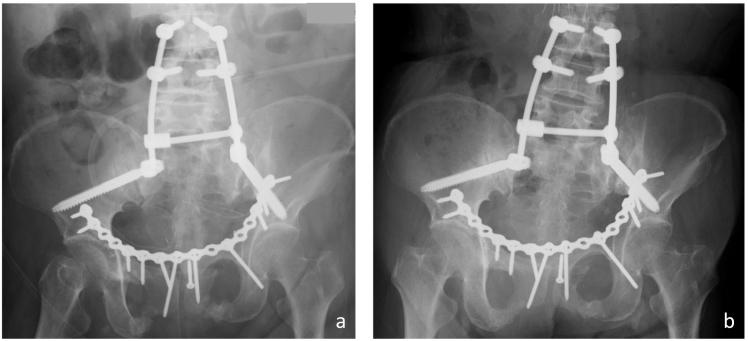

The incidence rate of bladder rupture associated with pelvic ring fractures is reported to be about 5-10%, mostly occurring at the time of injury. Fragility pelvic ring fractures are reported to increase fracture displacement or become nonunion if they are treated inadequately. Few case reports on bladder rupture associated with fragility pelvic ring fracture have been published. We report a rare case of delayed bladder rupture associated with a fragility fracture of the pelvis. A 65-year-old female felt right hip pain without sustaining any trauma. She was diagnosed with a right pubic rami fracture. However, her pain deteriorated, and a sacral fracture was identified one month later. She was prescribed teriparatide, but her pain worsened and she was referred to our hospital. She was diagnosed with fragility fracture of the pelvis (Rommens classification type IVb) and was treated operatively. During the surgery, her thin bladder wall, which was compressed by a displaced pubic fragment, was torn and repaired. This is the first report describing a fragility fracture of the pelvis associated with a bladder rupture. Our treatment led to a successful result.

据报道,与骨盆环骨折相关的膀胱破裂发生率约为5%-10%,大多发生在受伤时。据报道,脆性骨盆环骨折若治疗不当会增加骨折移位或导致骨不连。关于脆性骨盆环骨折合并膀胱破裂的病例报告很少。我们报告一例罕见的与脆性骨盆骨折相关的延迟性膀胱破裂病例。一名65岁女性在未遭受任何外伤的情况下感到右髋疼痛。她被诊断为右侧耻骨支骨折。然而,她的疼痛加剧,1个月后发现骶骨骨折。她接受了特立帕肽治疗,但疼痛仍加重,随后被转诊至我院。她被诊断为骨盆脆性骨折(罗曼斯分类IVb型)并接受了手术治疗。手术过程中,她被移位的耻骨碎片压迫的薄膀胱壁被撕裂并进行了修复。这是第一例描述与膀胱破裂相关的骨盆脆性骨折的报告。我们的治疗取得了成功。